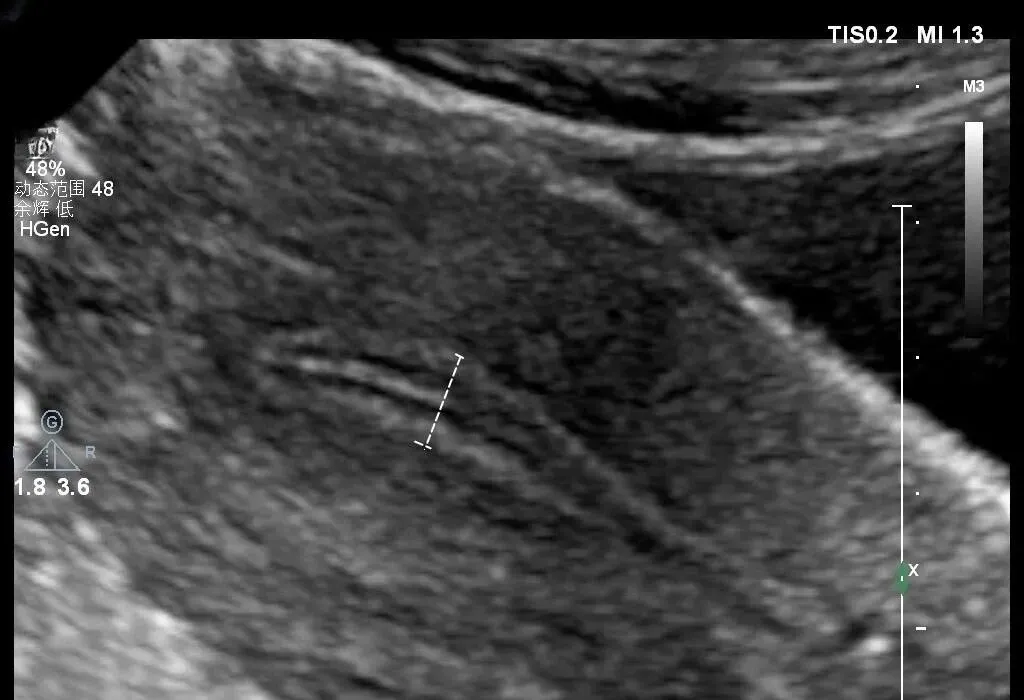

●子宫前后径的测量

★ 测量标准切面:于子宫长径测量切面测量,即子宫正中矢状切面

★ 测量方法:测量与子宫(宫体)长径相垂直的最大前后距离